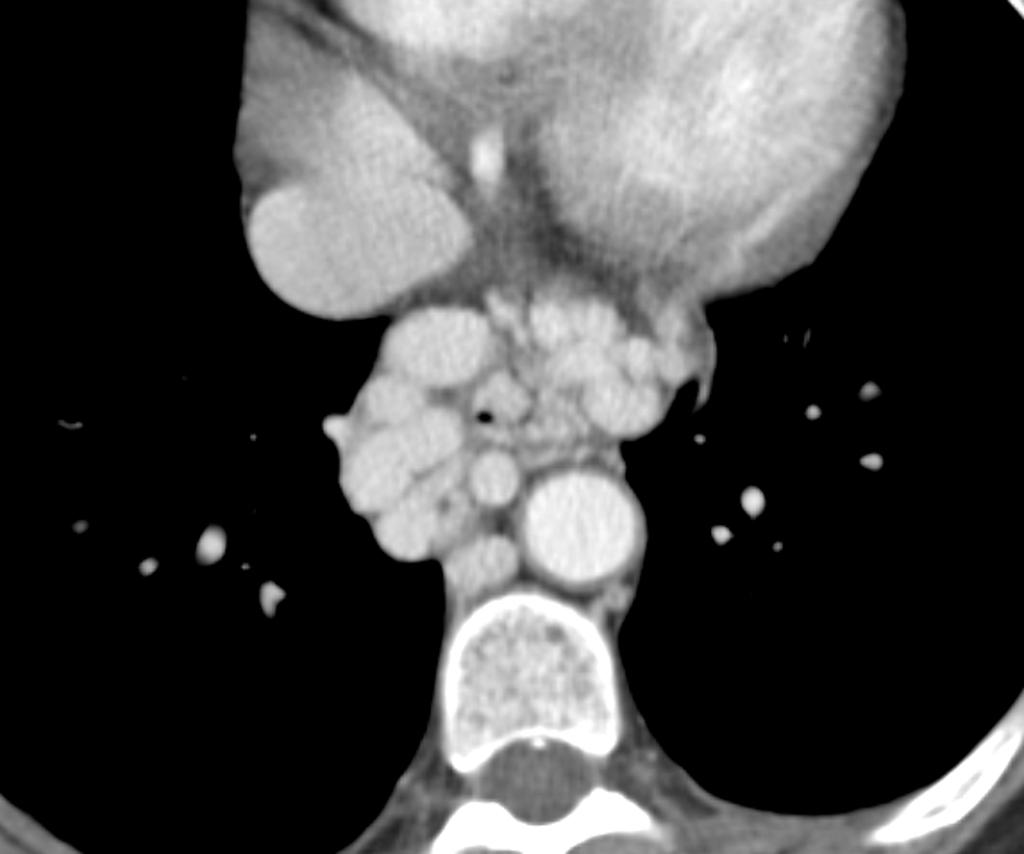

Hypertension portale : varices oesophagiennes

Case courtesy of Dr Roberto Schubert, Radiopaedia.org. From the case Oesophageal varices